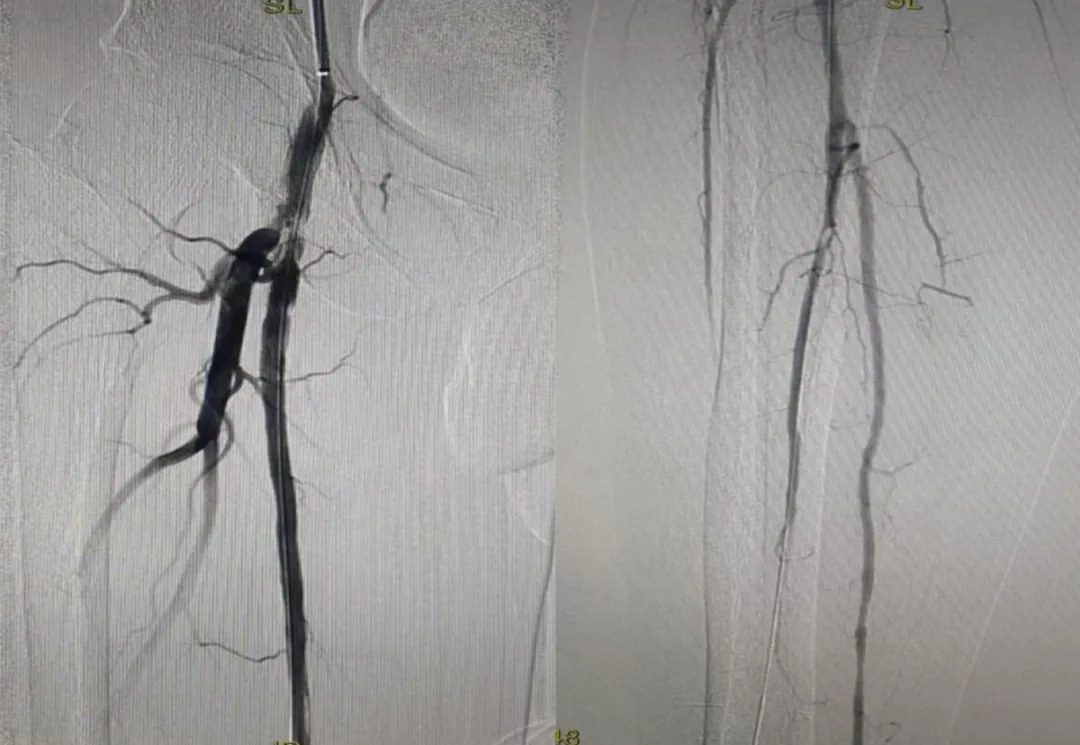

隨著血管的重新通暢

血液如歡快的溪流般

奔騰流淌

劉大叔的腿部

也迎來(lái)了轉(zhuǎn)機(jī)

就像久旱逢甘霖的大地

重新煥發(fā)生機(jī)

術(shù)后造影